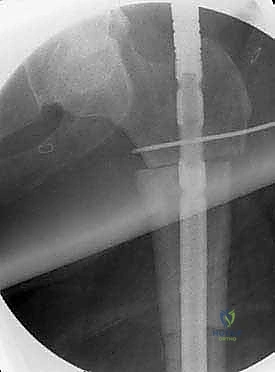

"Now, we'll define our osteotomy levels. Using fluoroscopy and our preoperative measurements, we'll place K-wires perpendicular to the shaft of the bone at the planned proximal and distal osteotomy levels. This provides a precise, reproducible guide for our cuts. Take care to avoid excessive damage to the periosteum adjacent to the planned osteotomy, as this is crucial for future healing."

Performing the Osteotomy

"Power saw, please. We perform a transverse osteotomy with a power saw. Keep the saw blade constantly cooled with irrigant – saline works well – to prevent excessive heat generation. Thermal necrosis of the host bone can compromise healing and lead to nonunion. We want clean, perpendicular cuts. While stepped cuts are an option to increase host-allograft contact, they are more technically demanding, add surgical time, and can cause more periosteal damage. For most intercalary resections, a transverse cut is sufficient and allows for easier rotational adjustments."

Here, you can see the power saw making a precise transverse osteotomy. Note the constant irrigation to prevent thermal damage to the bone.